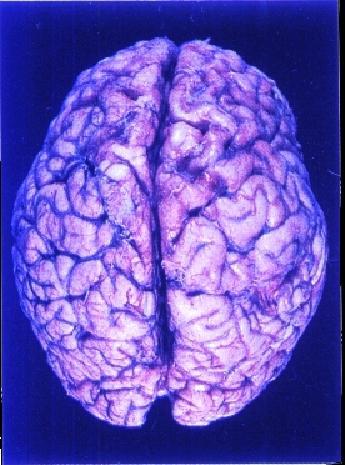

Nein, genau symmetrisch sind die, den Beobachtenden häufig rosa-grau erscheinenden, Hälften des Cerebrum (Grosshirns) nicht! Durch einen (Quer-)'Balken' (Corpus Callosum), aus 'weissen' Nervenfasern, verbunden, sind beide 'Hemisphären' weitgehend vom sehr falten- und windungsreichen Neokortex (der 'Großhirnrinde') umgeben, - dessen 'Feldern' allzu gerne ordnend und mit (letztlich neuro-)wissenschaftlicher Akribie, die hauptsächliche 'Zuständigkeit' für bestimmte Aufgabenbereiche 'zulokalisiert' werden. |

Draufsicht – Nase oben |

Diese, mit Abstand, grössten, zum Gehirn des Menschen gerechneten, Teile (85%) bedecken bzw. umschliessen wichtige andere (Gehirn-)Regionen, mit denen sie vielfachst verbunden - hervorragend geschützt und gedämpft, in Flüssigkeit schwebend, im Schädel gelegen – zusammenarbeiten. |

Großhirn (Cerebrum) 4/5 d.h. 85%

der Hirn-Masse aus zwei (per

'quer-Balken') verbundenen Hälften

bestehend Balken (Corpus Callosum) verbindet beide Hälften (zwischen ihnen) im Bereich des Großhirns

Es liegt über den restlichen Hirnteilen und weist viele Längs- und Querfurchen auf

beide Hemisphären sind (normalerweise) über den 'Balken' verbunden

es lassen sich Leistungszentren (spezialisierte Felder) einigermassen lokalisieren.

Schließlich stellt das Großhirn bzw. die Großhirnrinde den phylogenetisch jüngsten aber

auch den größten Teil dar und ist für die höheren psychischen Prozesse wie Wahrnehmung, Gedächtnis, Lernen, Denken und Sprache etc. unentbehrlich. Von seiner Lage her

wölbt es sich über die anderen Gehirnabschnitte.. .... Sogenannte Sulci

(Furchen) trennen die Hirnwindungen voneinander. So wird das Großhirn durch eine

tiefe Längsfurche (Fissura longitudinalis) in zwei

Hemisphären (linke - rechte) unterteilt, die alleine durch den Balken (CC) miteinander

verbunden sind. Dieser macht eine effiziente Zusammenarbeit beider Hemisphären möglich.